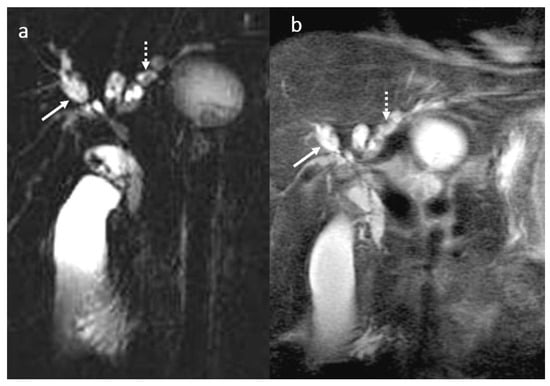

3.5. Biloma and Bile Leaks